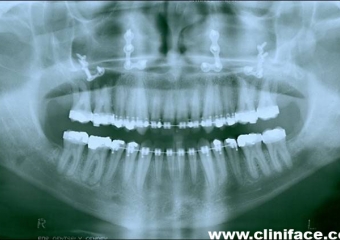

Raio X panorâmico final